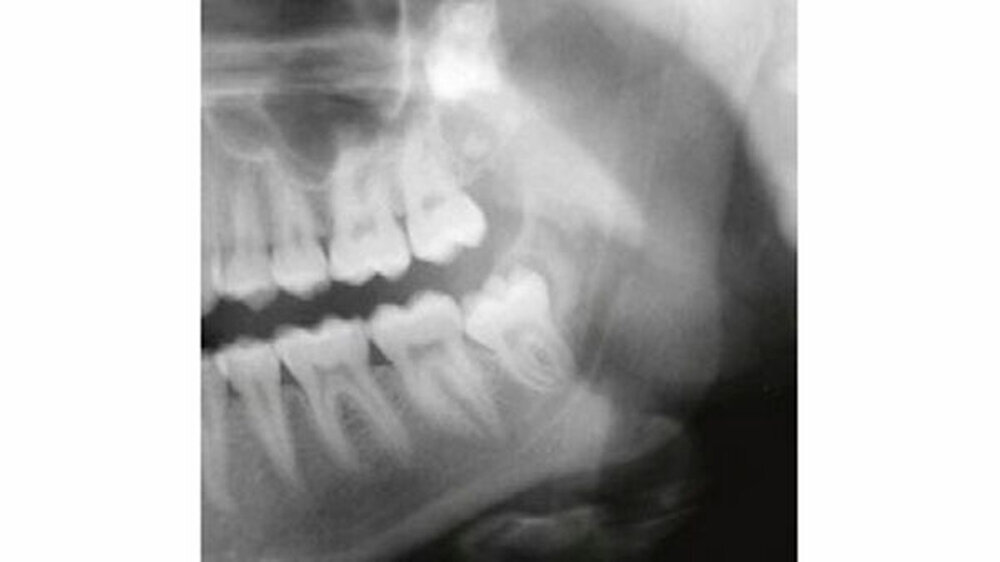

Auf dem mitgelieferten vier Jahre zuvor erstellten Orthopantomogramm (OPT) waren noch keine Hinweise auf das Vorhandensein einer Veränderung regio 32-34 sichtbar (Abbildung 2). Ein Jahr später konnte anhand des OPT bereits eine radioopake Struktur regio 33, 34 festgestellt werden (Abbildung 3). Auf dem aktuellen OPT und digitalen Volumentomogramm (DVT) zeigten sich regio 32-34 lingual multiple, rundliche, unterschiedlich große Radioopazitäten, umgeben von einer radioluzenten Zone.